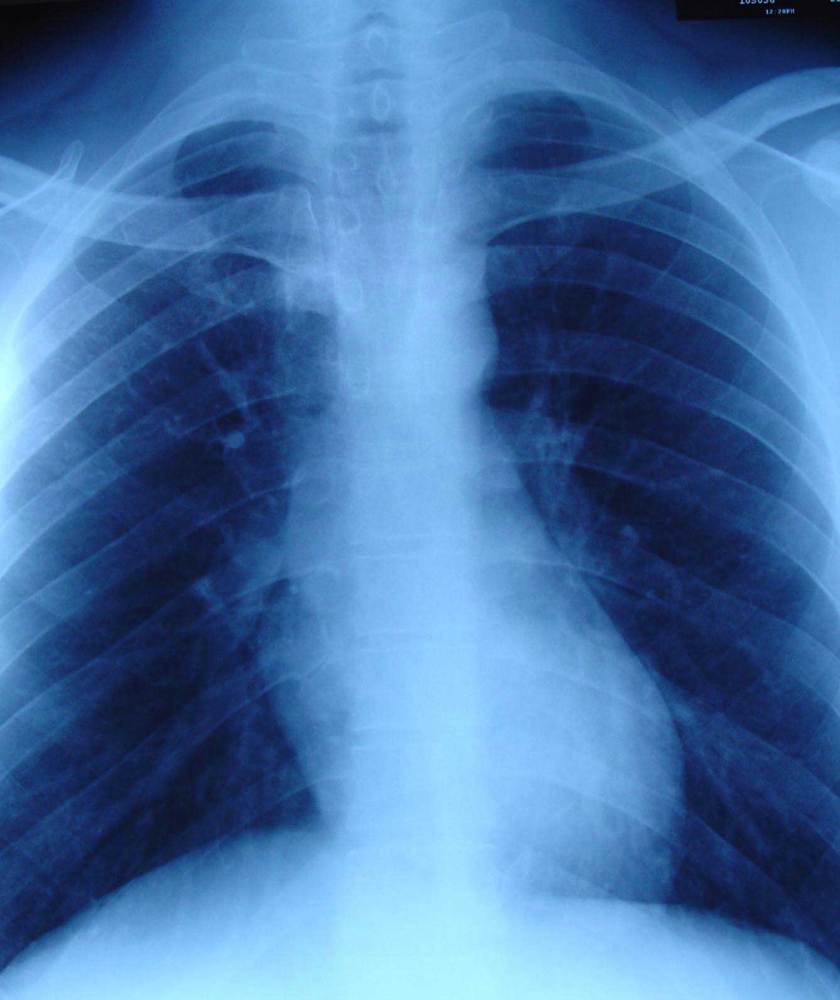

However, his illness did not go away. Blood test result on 1 December 2008 showed CEA = 15.9 (high) while a CT scan on the same day showed:

1. multiple peripheral nodules in both lungs, predominantly the upper lobes. Conclusion: lung metastasis.